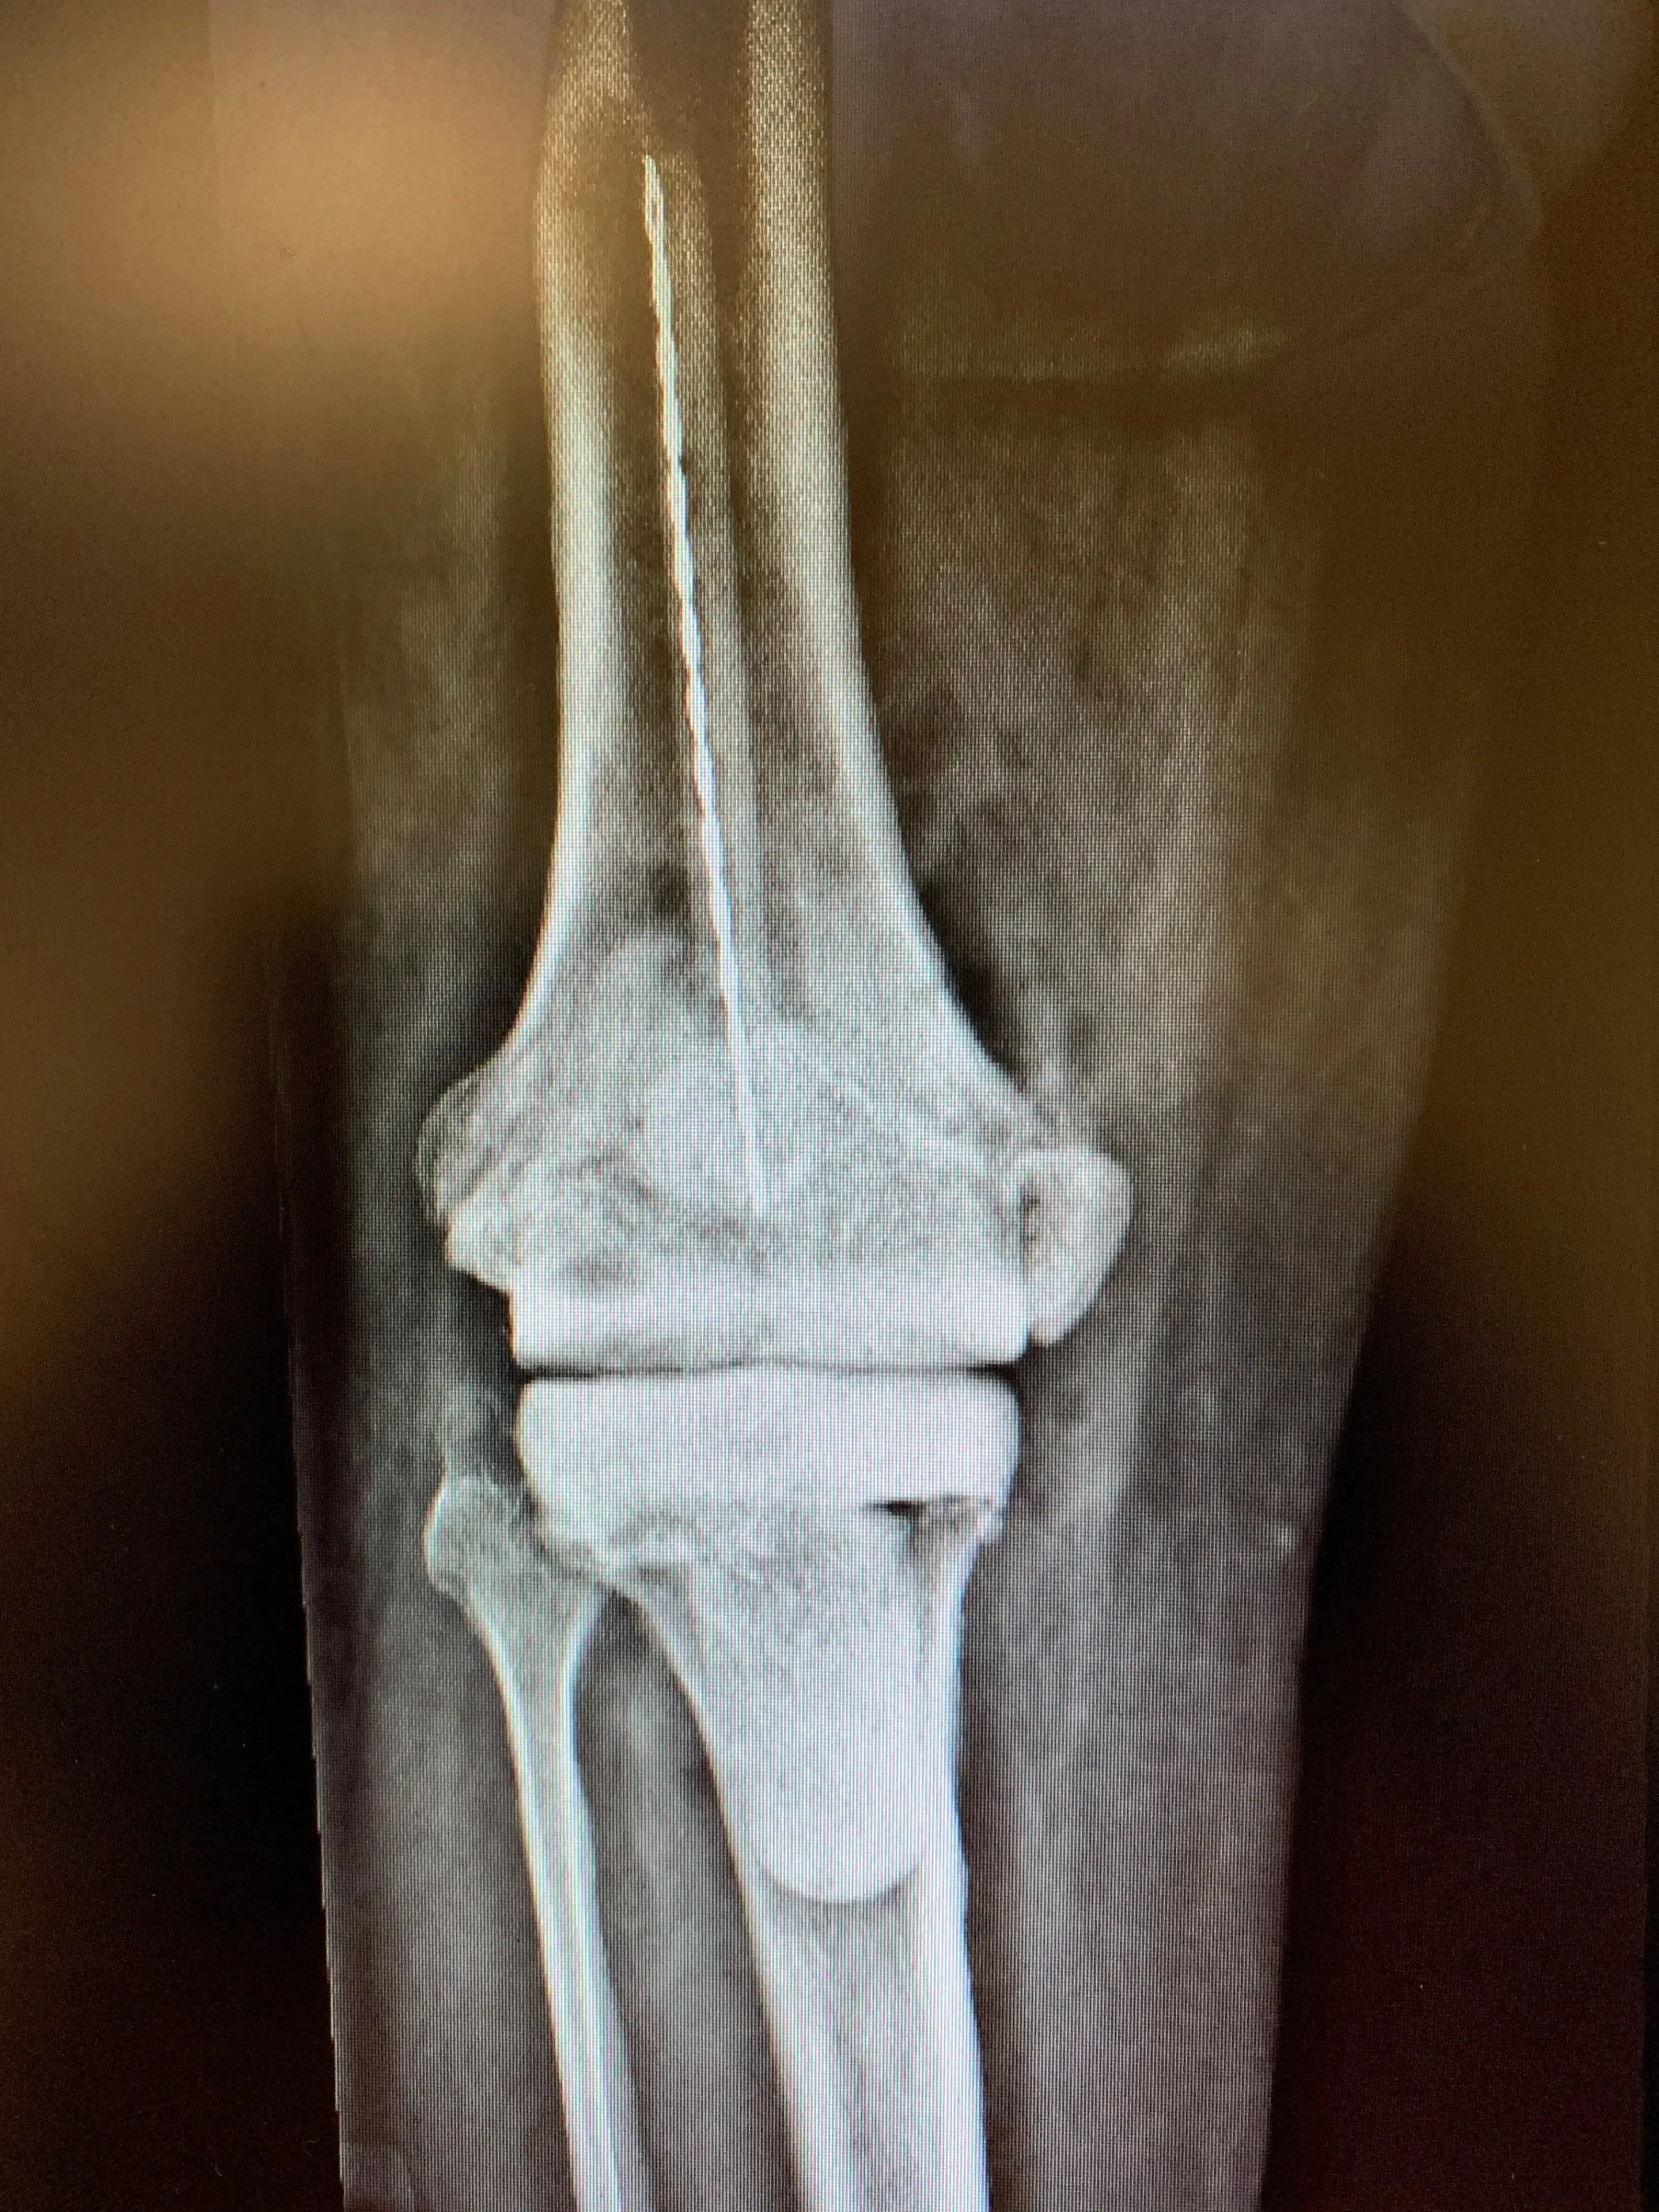

X-rays revealed an appropriately sized and positioned Revision Total Knee Replacement prosthesis with a resurfaced patella and no obvious signs of loosening or periprosthetic fracture.

Pre-op

Treatment of infected knee replacement. A staged reconstruction in a 64-year-old male.